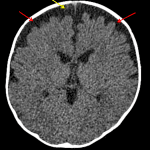

Age: 5 months

Sex: Male

Indication: Fever

Findings

- Enlargement of the subarachnoid spaces overlying the bilateral frontal convexities

Diagnosis

- Benign enlargement of the subarachnoid spaces of infancy (BESSI)

No acute intracranial abnormality. Findings typical of benign enlargement of the subarachnoid spaces of infancy (BESSI), a self-limited condition that typically resolves by 18-24 months of age. If there is ongoing high clinical concern for intracranial infection, consider brain MRI with and without contrast for further evaluation.